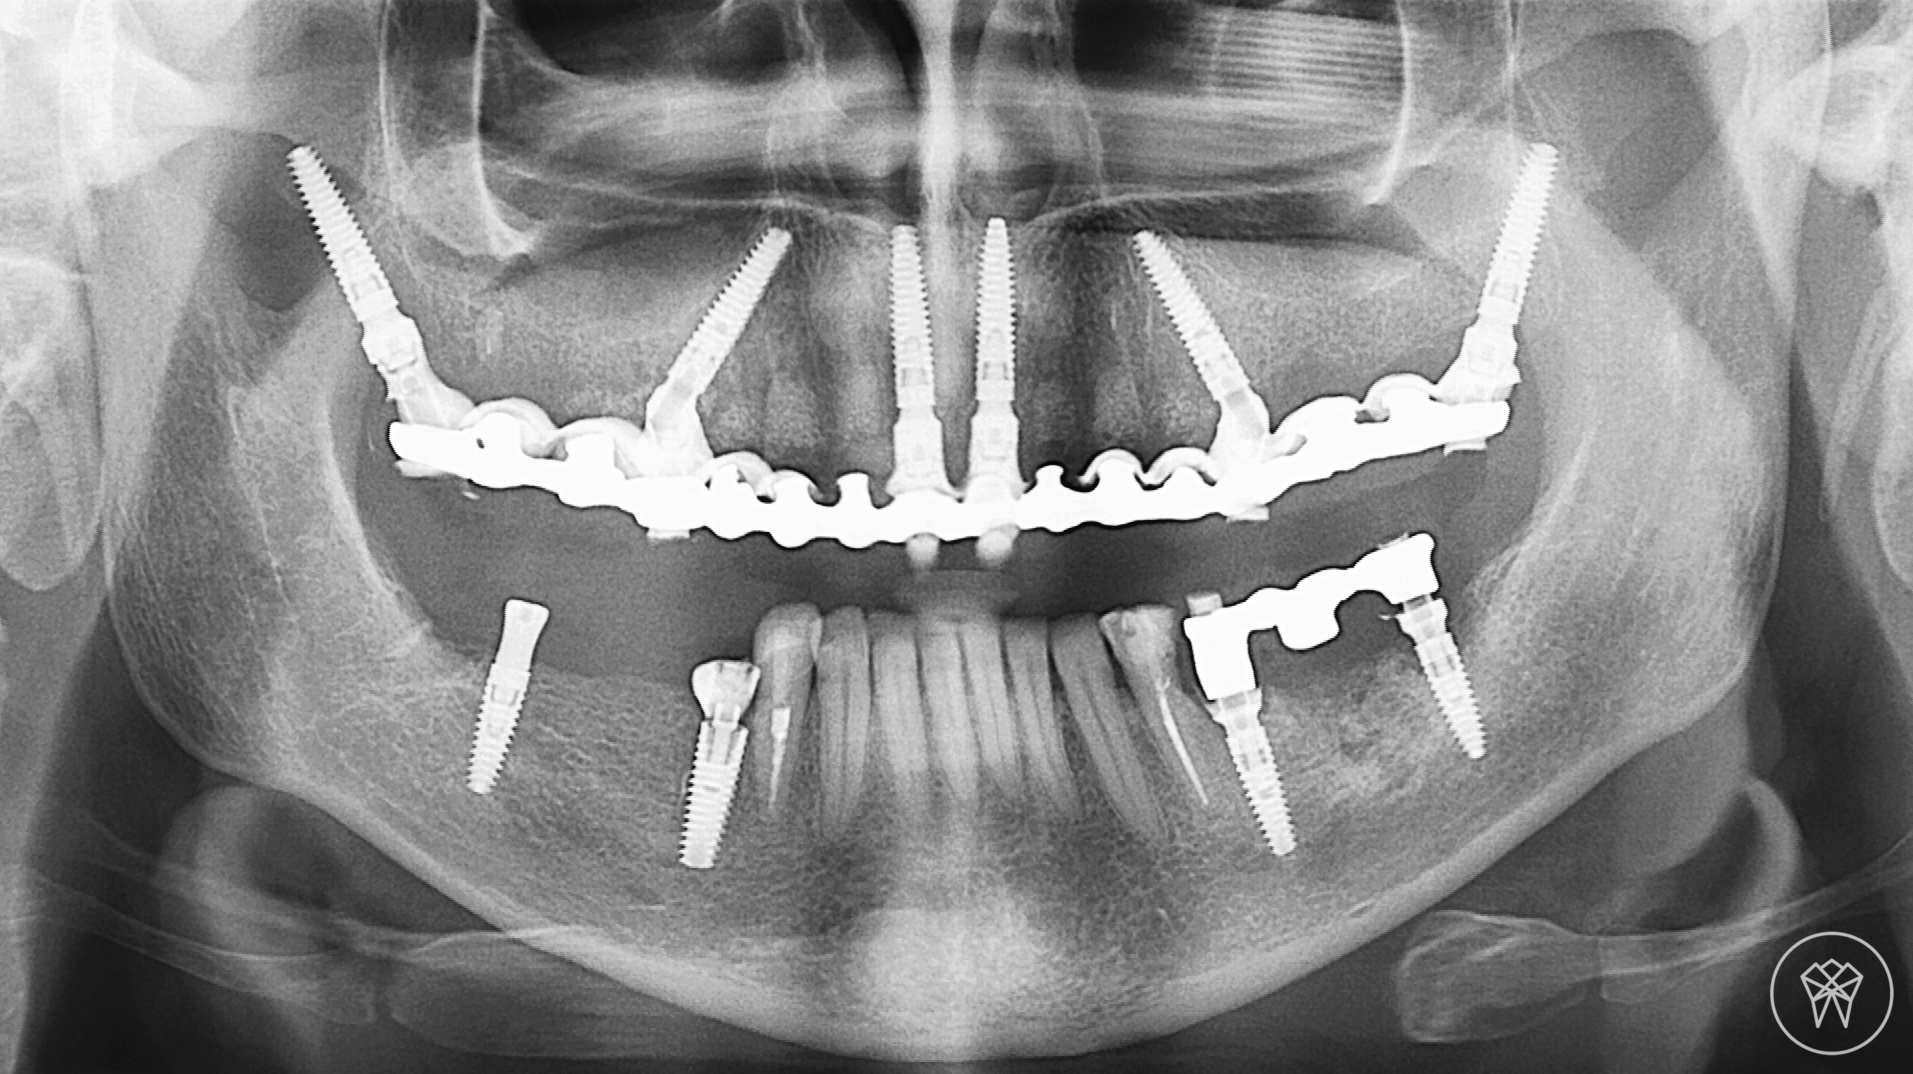

All in six 111 фото